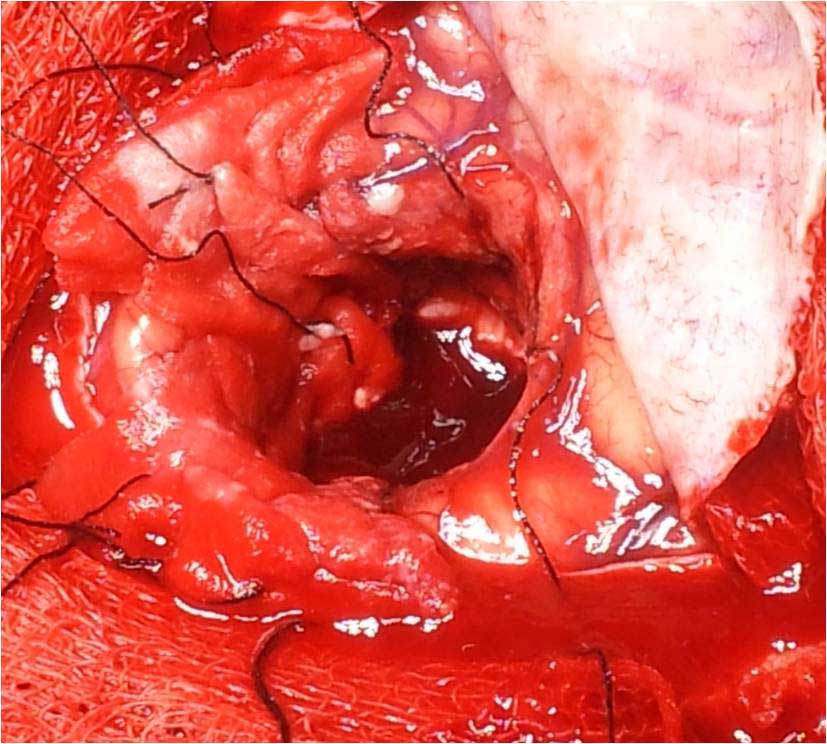

Brain Abscess Brain Abscess Post OP 2 Clinical Intra OP ,After Excising The Granuloma Intaop Scalp Abscess CT Scalp Abscess Cerebellar Abscess Post OP Clinical Cerebellar Abscess Brain TB Granuloma Post OP CT Scan Brain Infection Brain Abscess Preop MRI 2 Brain Abscess PRE OP Clinical 1 Brain Abscess PRE OP Brain Abscess Intraop 2 Brain Abscess Following Shunt Temporal Abscess T2W of TB Granuloma Scalp Abscess Preop CT Marking PRW OP MRI of TB Granuloma Post OP Clinical Photo Post OP Cerebellar Abscess Post OP Brain Abscess Intraop Specimen of Granuloma